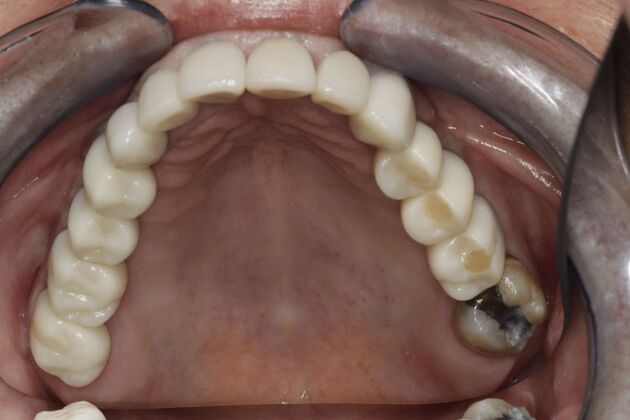

Removable partial dentures were left in a drawer for year and never worn because of their fit, food getting under them, and difficulty with speech. This patient finally got tired of not having back teeth to chew with and came to Dr Nordhus to discuss implant options. Due to her lack of bone structure a specialist placed the implants where her natural teeth were missing in the back. Dr Nordhus then restored her entire mouth to achieve her desires to be able to chew and have a beautiful smile.